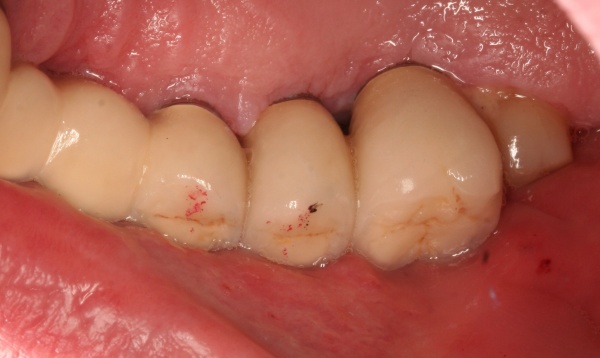

Bevor die Implantatprothetik angefertigt wird, sollten zahnärztlicherseits die periimplantären Weichgewebsverhältnisse erneut geprüft und bewertet werden. Sofern keratinisierte Gingiva periimplantär fehlt, sollte spätestens zu diesem Zeitpunkt ein weichgewebschirurgischer Eingriff (BGT, FST) erfolgen (Abb. 6).

Bevor die Implantatprothetik inseriert wird, überprüft der versorgende Zahnarzt, ob die periimplantären Strukturen sondiert und insbesondere durch den Patienten gepflegt werden können. Dies lässt sich bereits auf dem Meistermodell nach Abnahme der Silikonzahnfleischmaske kontrollieren. Die Krone sollte idealerweise dem Emergenzprofil des Implantates oder des Abutments folgen (Abb. 7a/b).